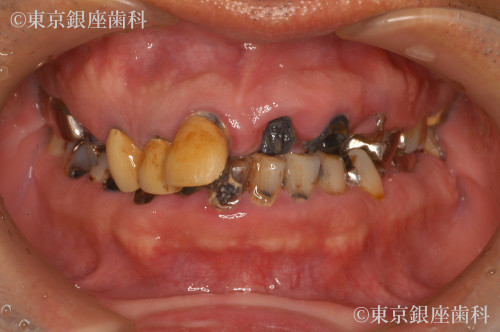

ボロボロの歯の症例

Before

After

40代 男性

疾患 歯周病

施術内容 ワンデイインプラント

治療期間 11カ月 費用 620万円(税込)

虫歯、歯周病

部分ワンデイインプラント、セラミック治療、メタルフリー、歯周治療